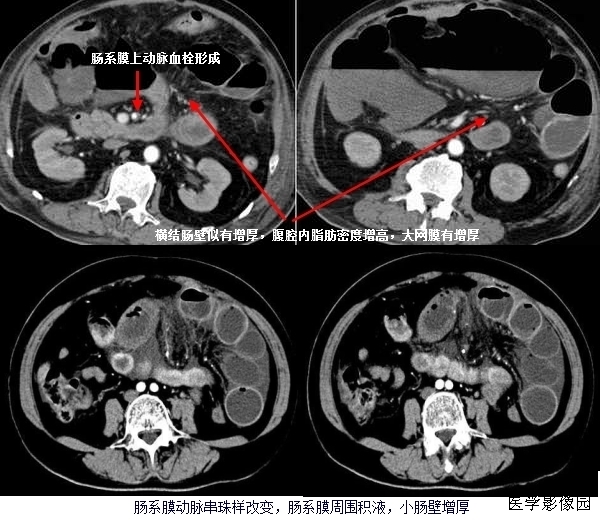

上两幅图:肠系膜上动脉栓塞

下两幅图:十二指肠扭转致肠壁增厚、肠系膜水肿